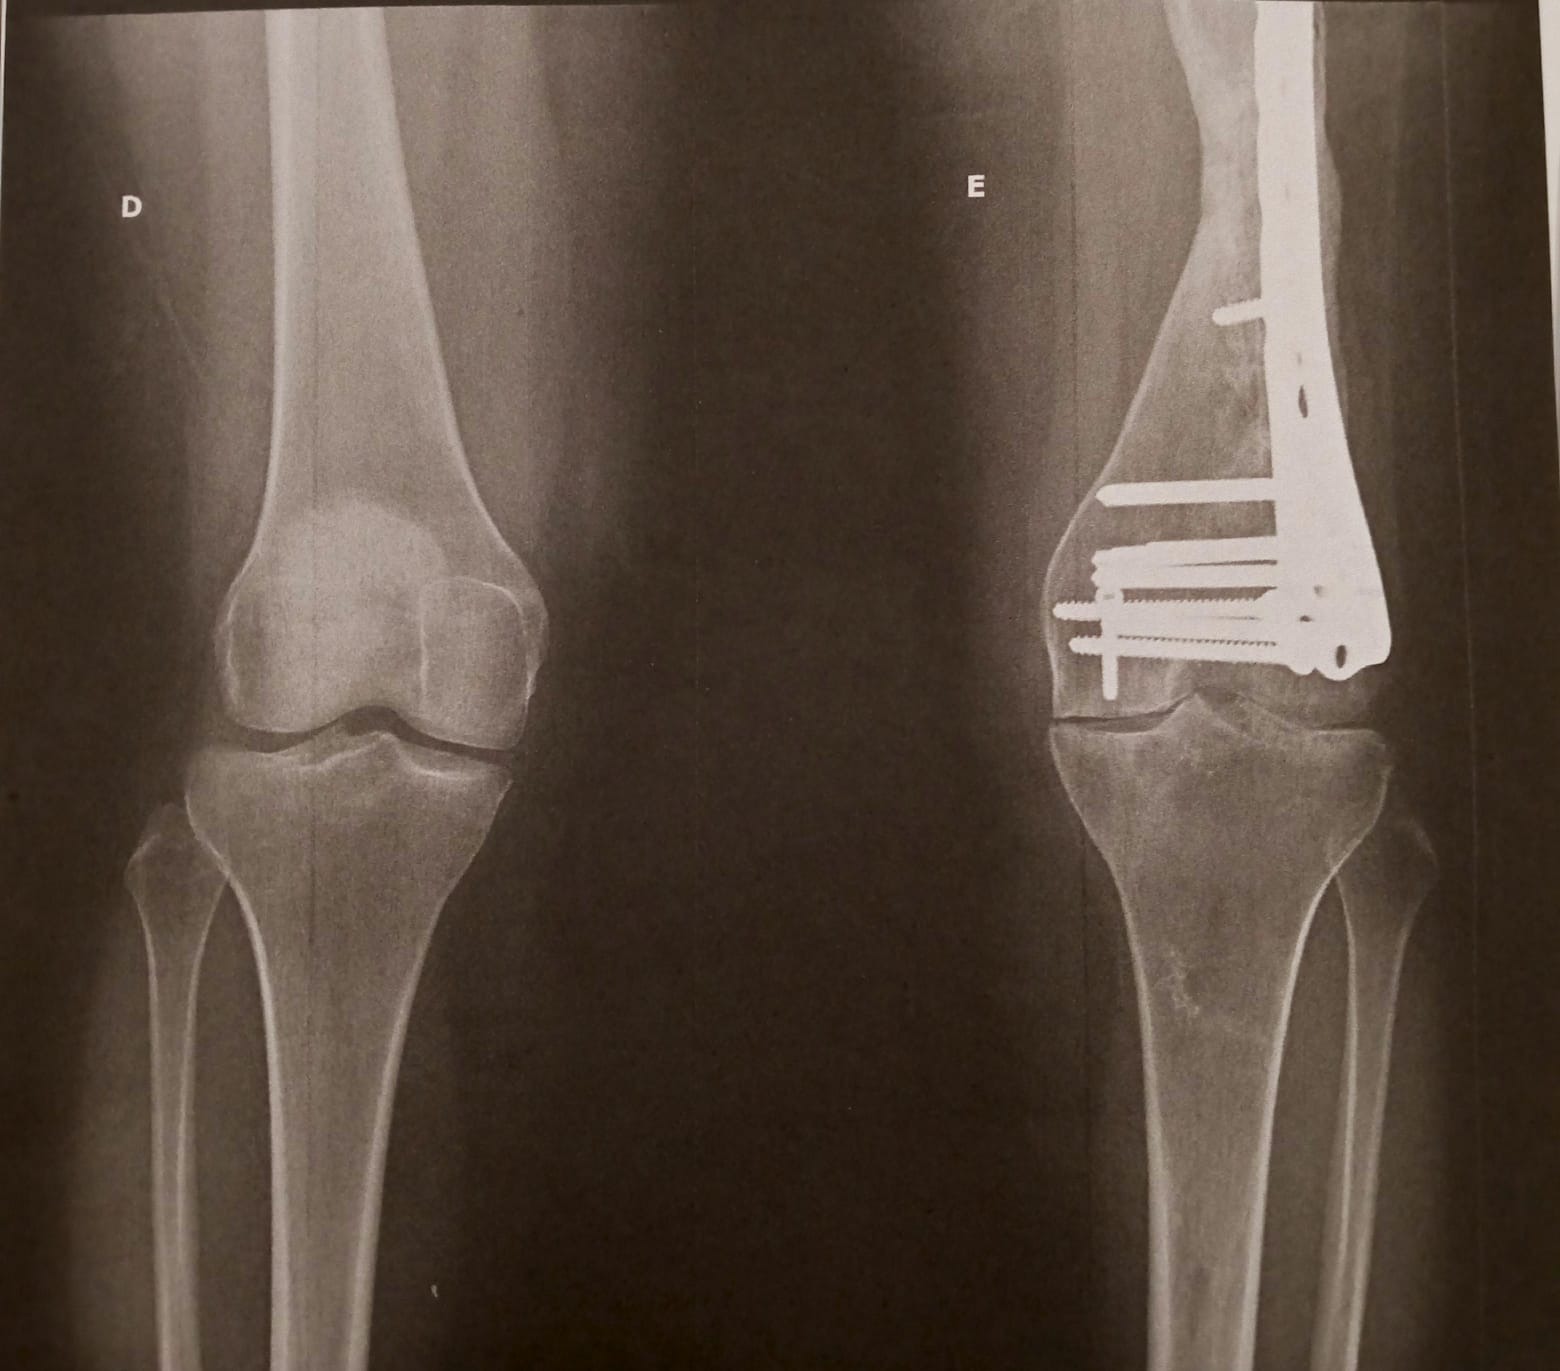

-Fracturas graves en su pierna

-Varias cirugías

Ella nunca se rindió. Siempre creyó que podía volver a caminar aunque no como antes pero sin dolor. Con el tiempo, las secuelas del accidente han pasado factura: hoy sufre artrosis avanzada, consecuencia directa de aquel choque. Los médicos han sido claros: necesita un trasplante de rodilla con urgencia.